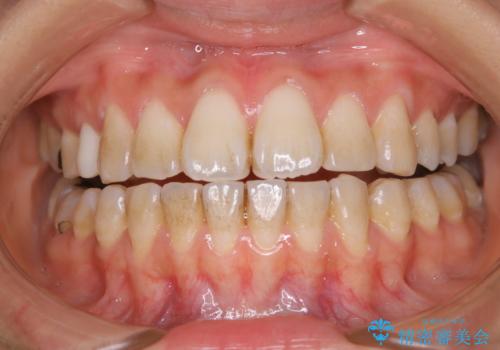

矯正治療開始前のPMTC

治療症例の内容

- 矯正治療前にステインを取りたいとのことで来院されました。ステインは前歯のみだったため、PMTC30分コースを行いました。

PMTCとは、歯科の専門家が器械を使用して行う歯のクリーニングのことです。普段の歯磨きでは取り切れない溝、キワなどの細かい部分も徹底的に除去します。ステインや歯石などが付着したままだと、虫歯や歯周病の発見がしずらいことがあります。特に矯正治療前には、念入りな虫歯や歯周病チェックが必要なため、PMTCでしっかりと汚れを除去しておくことが大切です。